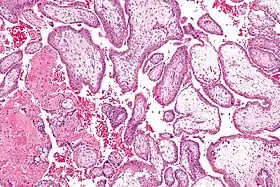

![]() صورة مجهرية تظهر الزغابات المشيمية. تكبير متوسط. صبغة الهيماتوكسيلين والأيوزين. | |